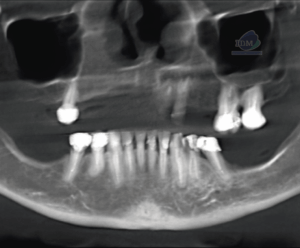

Paciente femenino de 53 años acude para una evaluación general. A la evaluación de la tomografía volumétrica (cone beam) bimaxilar en los cortes axiales (Figura